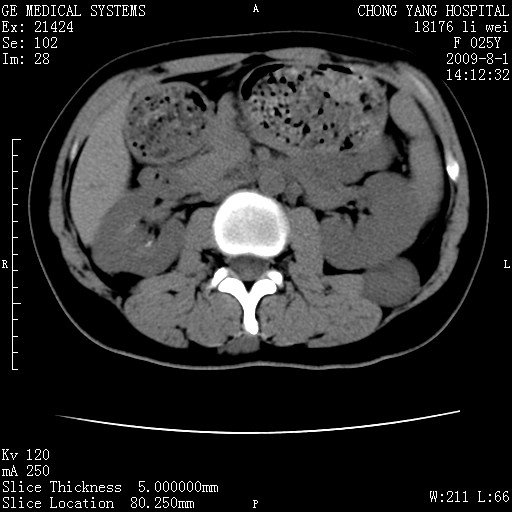

以下是引用pujunzhi在2009-8-1 20:23:00的发言:[br]胸椎旁及背部肌间良性病变,范围广,边界清,沿肌间生长,考虑淋巴管瘤、血管瘤,建议增强扫描。

以下是引用拾荒者在2009-12-30 21:45:00的发言:[br]ct21383:神经纤维瘤病( nf) [br] [br] 神经纤维瘤病。四肢都有,影响美观,四肢上的手术了。[br] [br] [br]谢谢!